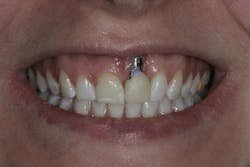

- High smile lines (figure 4)